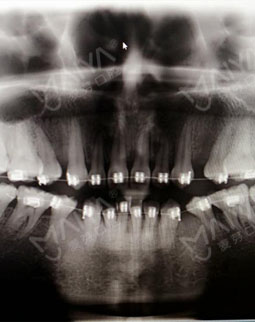

2016/07/15 矫正方案制定

终于又等到周末啦!这一次作为患者来到麦芽,进门后客服笑盈盈的给我开门,然后填了单子,就有专人带我去见麦芽的主任了,主任和照片上一样平易近人,让我和医生的距离一下子就拉近了,耐心的听了我的苦恼。为了看一下我的牙齿,客服带着我还拍了片,这是我在之前矫正的时候没有的环节。看到电脑上显示的自己的牙齿,对这种高科技的东西着实惊了一下,相信很多人和我一样都觉得矫牙就是医生看一下,就开始戴牙套了,但是这一刻我终于明白了,矫牙并不是你以为,技术设备医生这些都很重要。

张主任指着片子说,牙齿错过了最好的矫牙年龄,而且又矫牙失败,我的属于疑难矫正了,但是还是可以矫正好的!然后为了减轻我的痛苦,让我继续戴现在的牙套,但是要分阶段调整一下,我非常开心感觉牙齿还有救,当天医生给我调整好之后,牙齿就舒服了很多,我的心情也是多云转晴!!!